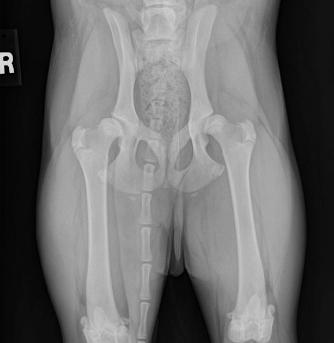

OFA (left) and PennHIP (right) radiographs on the same canine patient. The hips look reasonable on the OFA images (left) but the extreme laxity is readily evident on the PennHIP radiographs.

This patient has had a unilateral total hip replacement.